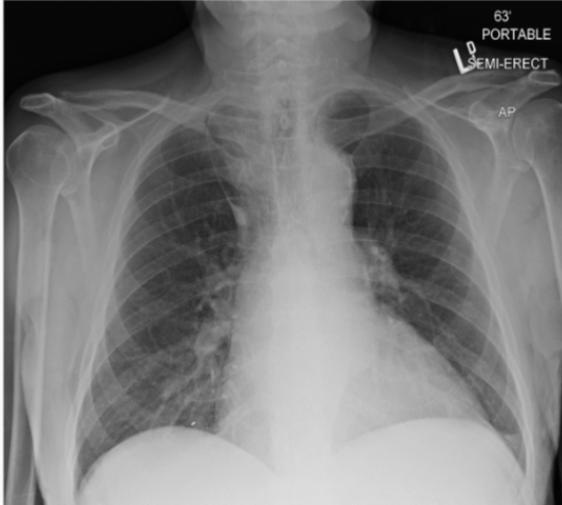

What is this patient presenting with?

Pulmonary edema—classically “Batwing” in appearance

(starts central, spreads outwards)